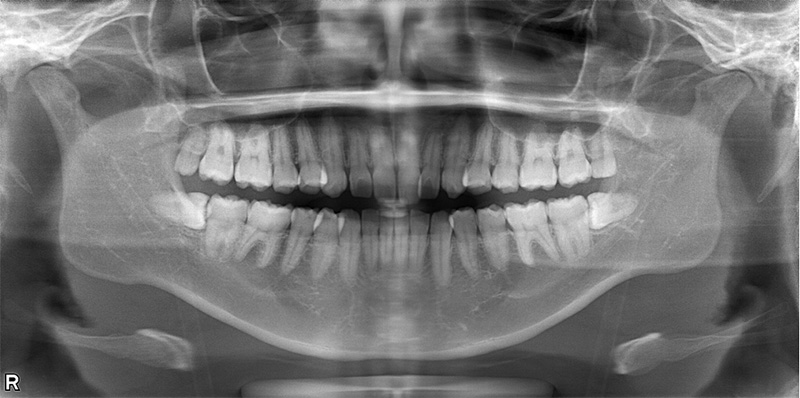

58歳女性

治療前

治療後

| 施術名 | インプラント治療 |

| 施術の説明 | インプラント治療とは、歯を抜いた所にチタン製の人工歯根を埋入し、新しく歯を入れる方法です。 |

| 施術の副作用 (リスク) | 腫れや疼痛を感じる、違和感を感じるなどの症状を生じることがあります。 |

| 施術の価格 | 53万円~+消費税 |